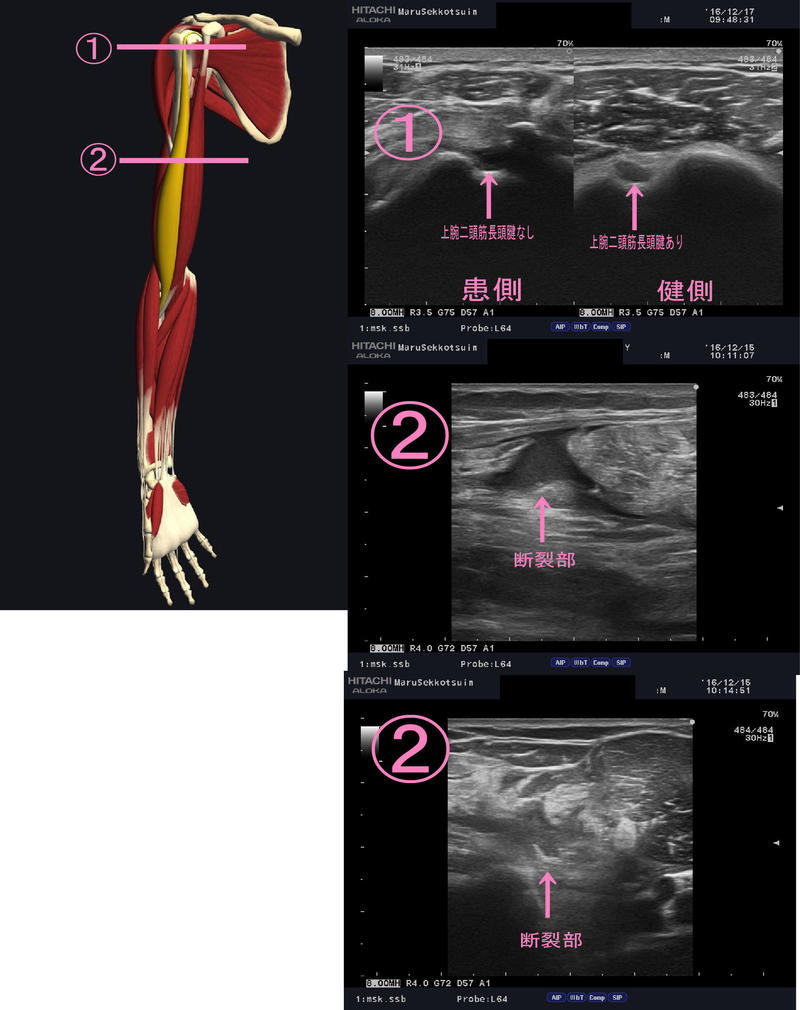

「上腕二頭筋長頭腱部の断裂」

ゴルフのプレー中、右上腕「力こぶ」の部分に、

激痛がはしり、その後、腫れてきたと御来院。

しっかり問診、触診をしたあと、

超音波画像観察装置(エコー)で確認。

結果・・・・・

やはり上腕二頭筋長頭腱部での断裂。